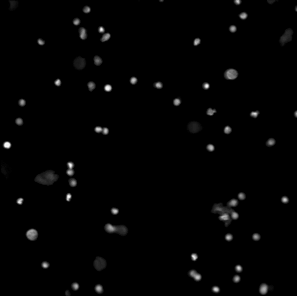

In Figure 14 (a), (d), (g) and (j) experimental data sets are shown. From the original image sets, consisting of three different fluorescent color channels, we extracted the tumor cell marker (green) and used those images as input for our multiscale segmentation approach. Although the difficulties vary between all images (inhomogeneous background, noise, cell clusters, mixture of size and intensity scales), we can process all images with our multiscale segmentation approach with the exact same parameters. This is essential for the development of a user-friendly (parameter-free) toolbox for CTC analysis. Note that the dim spots in image (d) are not cells but only pores of a filter used to collect cells (bright spots) and therefore it is not desired to segment them. The resulting spectral response functions for all four images are shown in Figure 14 (b), (e), (h) and (k) with a color coding corresponding to the coding used in the segmentation results in (c), (f), (i) and (l). The color coding of the response function shows that all objects which appear later in our segmentation and therefore belong to finer scales have a yellow to reddish color in the color-coded segmentation. The very large and intact cells are blue (with some small artifacts at the boundary) and smaller cells (or large fragments) are shown in light blue to green. We can nicely observe that the object colors cover the whole color scale range. For images that are more complex (e.g. (d) and (j)) also the spectral response function is more complex but the color-coded segmentation shows that nearly every object appears in one step and thereby has a clearly defined scale that we use as a feature in our classification approach. Here, we profit from the fact that not only Wulff shapes (perfectly circular objects) but also other eigenshapes appear in one step in our segmentation. Hence, this segmentation approach not only provides all contours automatically without any parameter adaptations but simultaneously also a simple classification of cells based on their size (scale resp. color/appearance time). This analysis can be applied to all color channels separately and be used together with more features in a subsequent automatic classification approach. The constants and can again simply be estimated a-priori from the data by a simple thresholding and averaging approach and are fixed throughout the iterative process.